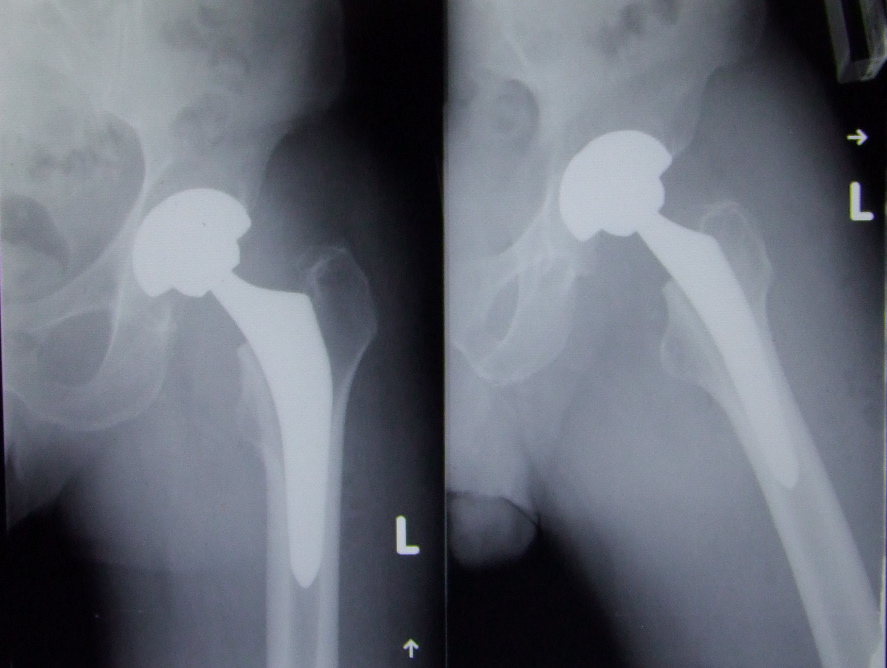

Le traitement chirurgical de la coxarthrose se résume dans la toute grande majorité des cas par le remplacement des deux composantes de l'articulation (arthroplastie total de de hanche).

La chirurgie trouve sa place dans cette pathologie en cas d'échec du traitement conservateur bien conduit ; le recours à la prothèse totale de hanche survient en moyenne au bout de 7-8 ans.

Enfin, la longévité de l'arthroplastie reste un facteur capital dans la qualité de l'intervention.

Cette dernière est en rapport avec les matériaux posés (tribologie), un positionnement de qualité des implants et l'activité du patient (patient jeune, hyperactif, obèse...).

D'un point de vue du choix des implants, l'utilisation de la céramique semble un choix judicieux du point de vue de la longévité.